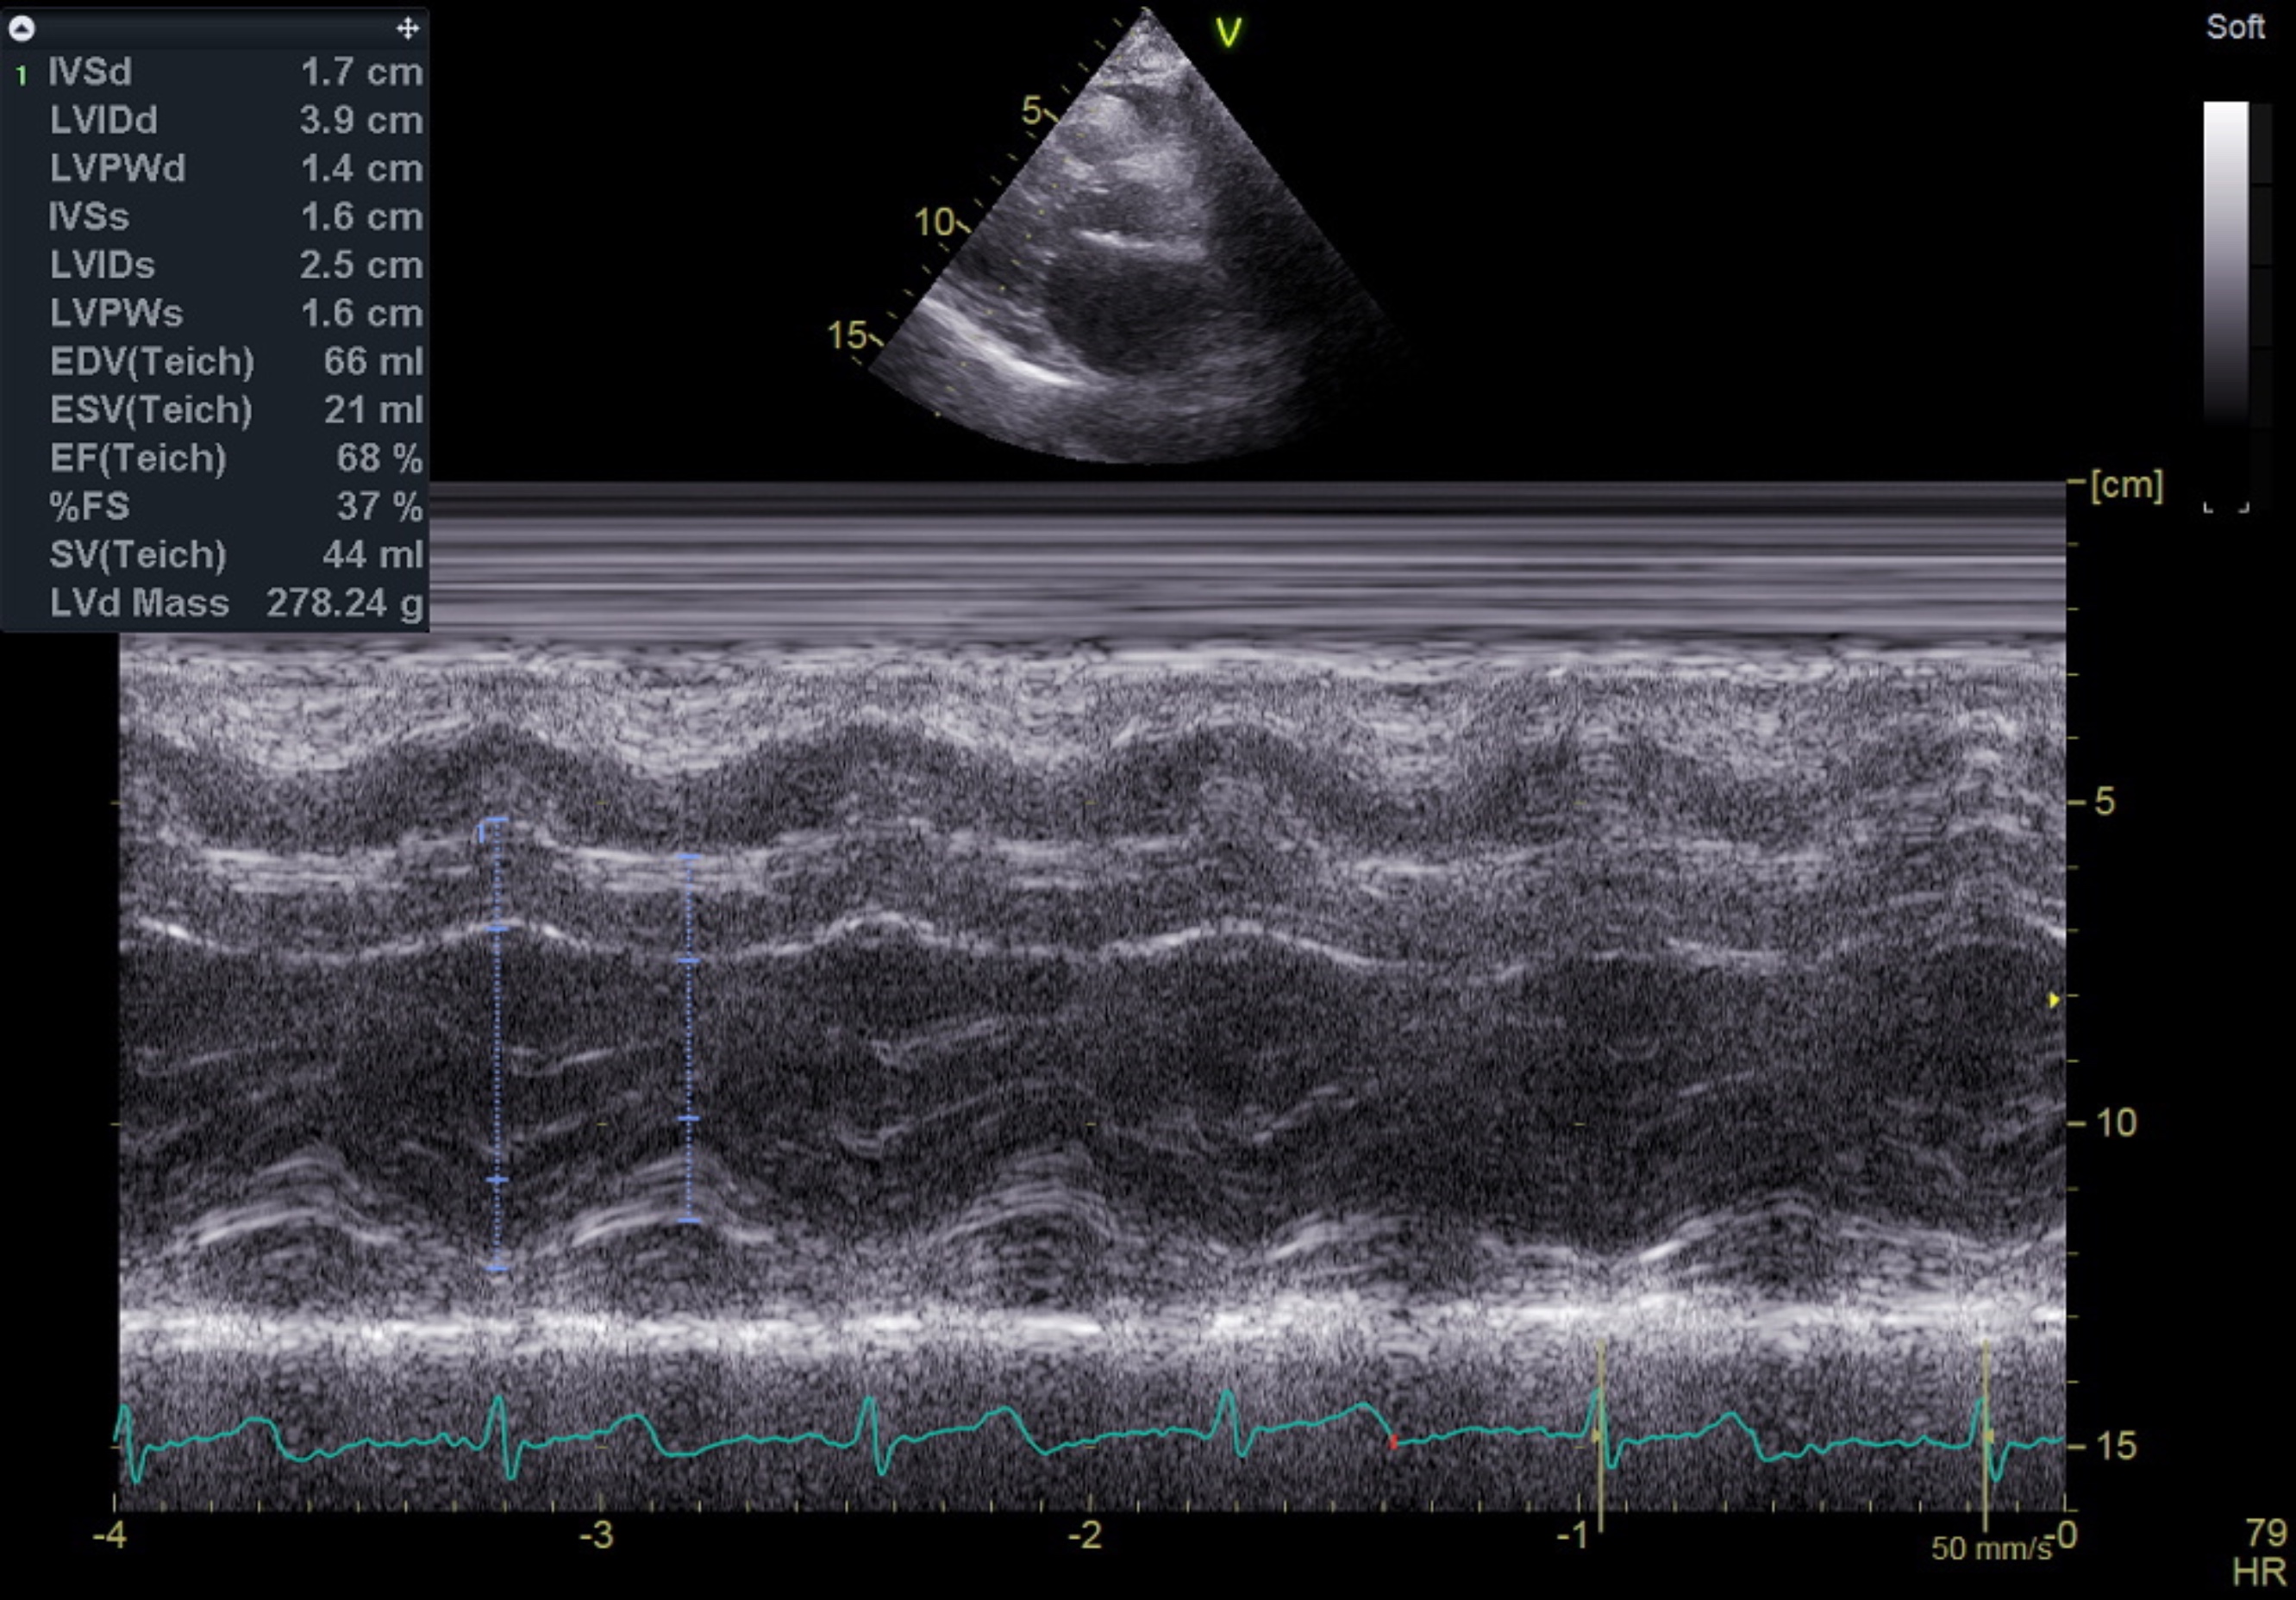

Relevant Test Results Prior to Catheterization

The initial electrocardiogram indicated sinus rhythm and normal axis without Left Ventricular Hypertrophy (LVH). No changes in the ST segment or T wave were noted. High-sensitivity troponin levels were serially elevated, suggesting Myocardial Infarction (MI). The echocardiography, however, showed no regional wall motion abnormality (RWMA) with preserved Left Ventricular systolic function (Ejection Fraction 55%). All cardiac valves were normal with no evidence of stenosis or regurgitation.